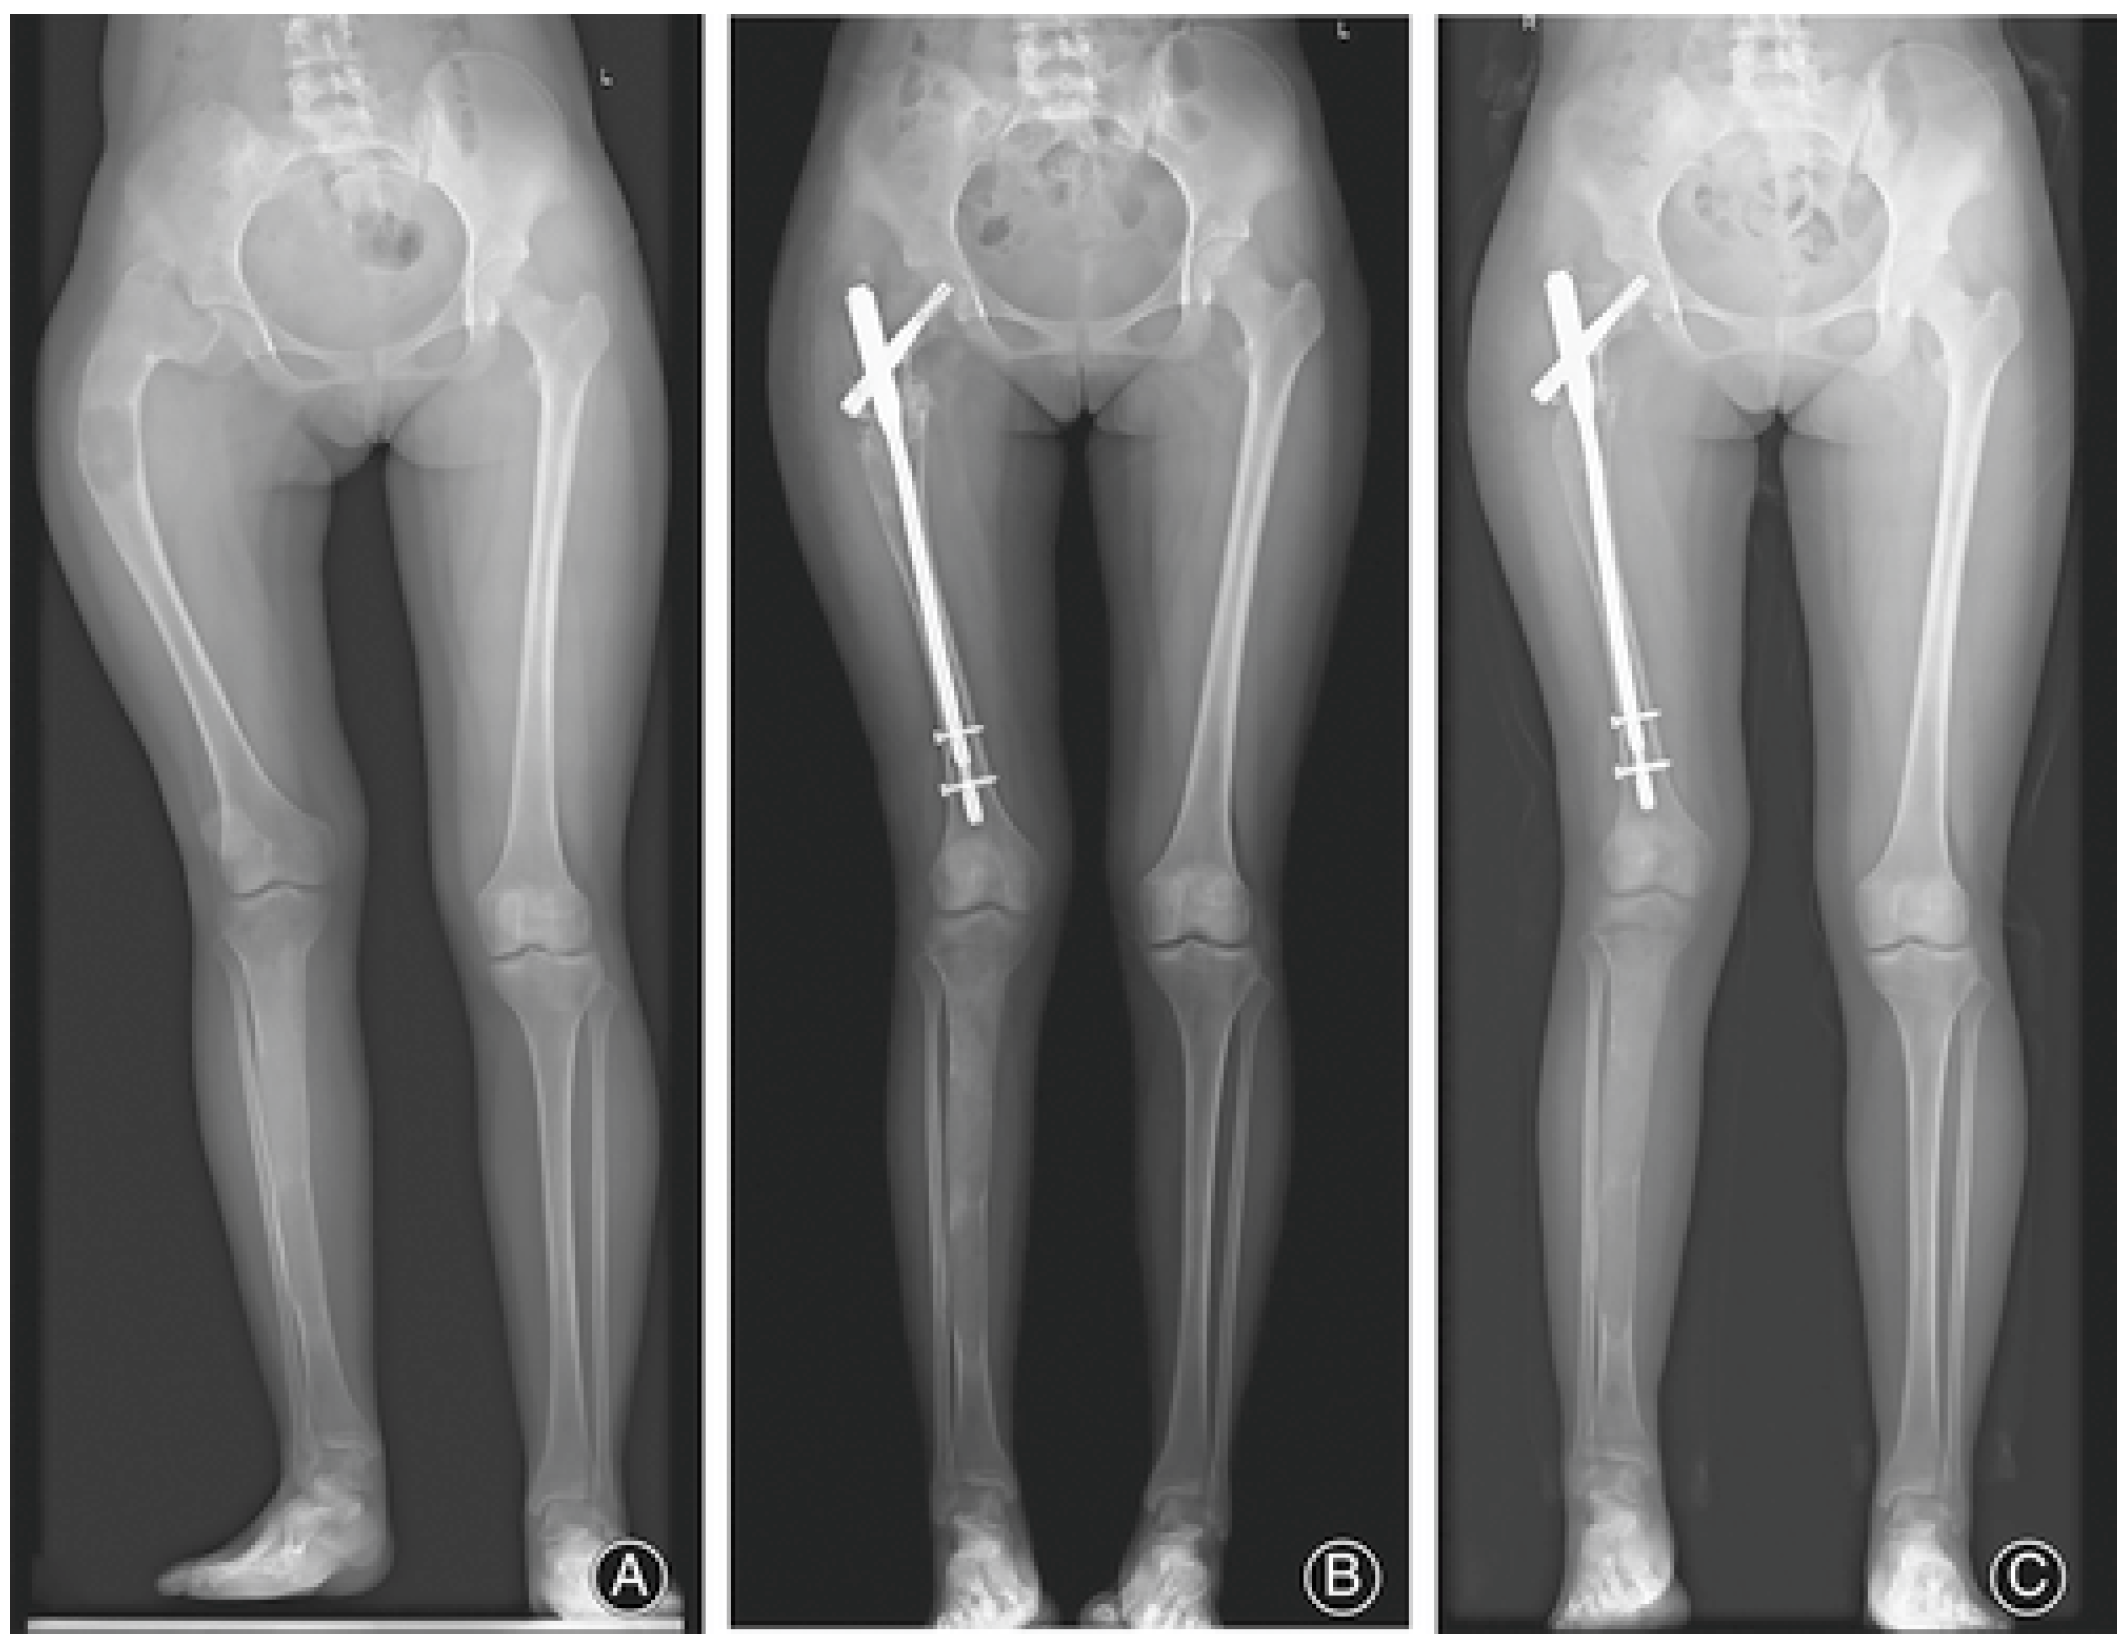

- Wang, Y.; Luo, Y.; Min, L.; Zhou, Y.; Wang, J.; Zhang, Y.; Lu, M.; Duan, H.; Tu, C. The West China Hospital radiographic classification for fibrous dysplasia in femur and adjacent bones: A retrospective analysis of 205 patients. Orthop. Surg. 2022, 14, 2096–2108. [Google Scholar] [CrossRef]

- Zhang, X.; Chen, C.; Duan, H.; Tu, C. Radiographic classification and treatment of fibrous dysplasia of the proximal femur: 227 femurs with a mean follow-up of 6 years. J. Orthop. Surg. Res. 2015, 10, 171. [Google Scholar] [CrossRef]

- Ippolito, E.; Farsetti, P.; Boyce, A.M.; Corsi, A.; De Maio, F.; Collins, M.T. Radiographic classification of coronal plane femoral deformities in polyostotic fibrous dysplasia. Clin. Orthop. Relat. Res. 2014, 472, 1558–1567. [Google Scholar] [CrossRef]